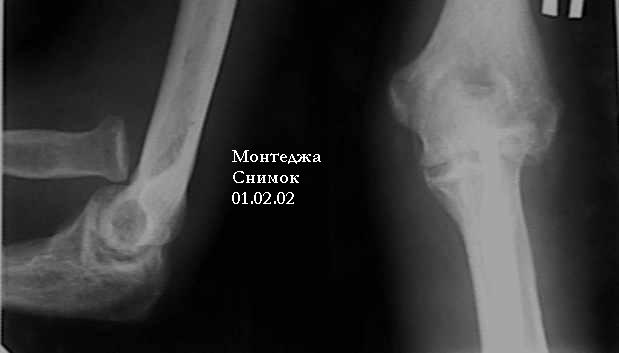

перелом Монтеджа

У больного травма в октябре 2001. Перелом Монтеджа разгибательный.Проведена операция металлостеосинтез пластиной, винтами локтевой кости. Вывих головки лучевой кости не диагностирован. В конце февраля 2002 г снята гипсовая повязка. Имеется ограничение сгибания до 115 градусов. Больной обратился в наше лечебное учреждение 07.02.02. Мы предложили ему оперативное лечение. Планируем провести резекцию головки лучевой кости. Есть мнение попытаться вправить головку лучевой кости, провести пластику кольцевидной связки, фиксисировать головку лучевой кости трансартикулярно спицей. Но боюсь, что в момент остеосинтеза была укорочена локтевая кость, поэтому необходимо будет провести резкцию в области диафиза лучевой кости, а затем провести остеосинтез лучевой кости. Рентгенограммы:

1; 2; 3; 4